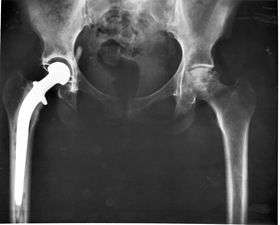

3. Class III devices generally require premarket approval (PMA) or premarket notification (510k), a scientific review to ensure the device's safety and effectiveness, in addition to the general controls of Class I. Examples include replacement heart valves, hip and knee joint implants, silicone gel-filled breast implants, implanted cerebellar stimulators, implantable pacemaker pulse generators and endosseous (intra-bone) implants.

Implants, such as artificial hip joints, are generally extensively regulated due to the invasive nature of such devices.